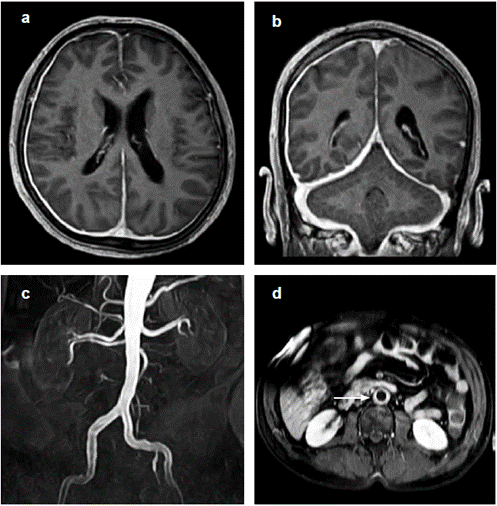

En los exámenes de laboratorio se demostró elevación de reactantes de fase aguda: eritrosedimentación de 117 mm/hora y proteína C reactiva de 3.33 mg/dl (VN 0-0.82). Los resultados de otros exámenes de laboratorio en suero, orina, líquido cefalorraquídeo e imágenes diagnósticas se muestran en las Tablas 1-3. El enfoque inicial estuvo orientado a descartar una arteritis de células gigantes, sin embargo el hallazgo de paquimeningitis (Figura 1) y de hiperproteinorraquia obligó a considerar múltiples diagnósticos alternativos incluyendo infecciones, neoplasias, enfermedades autoinmunes y procesos inflamatorios diversos. La presentación simultánea de paquimeningitis, aortitis y glomerulonefritis permitió estrechar nuevamente el espectro de diagnósticos diferenciales. La ausencia de pruebas de algún proceso infeccioso, la biopsia normal de arteria temporal y los anticuerpos contra el citoplasma de los neutrófilos (ANCA) del tipo mieloperoxidasa nos permitió diagnosticar al paciente con una vasculitis asociada con ANCA del tipo granulomatosis con poliangeítis (granulomatosis de Wegener). El paciente recibió esquema de inducción inicial con dosis altas de metilprednisolona más ciclofosfamida con mejoría de todos sus síntomas y normalización de sus alteraciones de laboratorio.

La resonancia magnética es la técnica imagenológica de elección para la confirmación, en la cual se observa engrosamiento local o difuso de la duramadre e incremento en la captación de gadolinio, con compromiso más frecuente de cerebro (80%) que de médula espinal (15%). El estudio del líquido cefalorraquídeo (LCR) muestra pleocitosis con predominio de linfocitos y/o concentración de proteínas elevadas en 63-70% de los casos, y la biopsia muestra usualmente cambios granulomatosos inflamatorios acompañados o no de vasculitis 37,39.